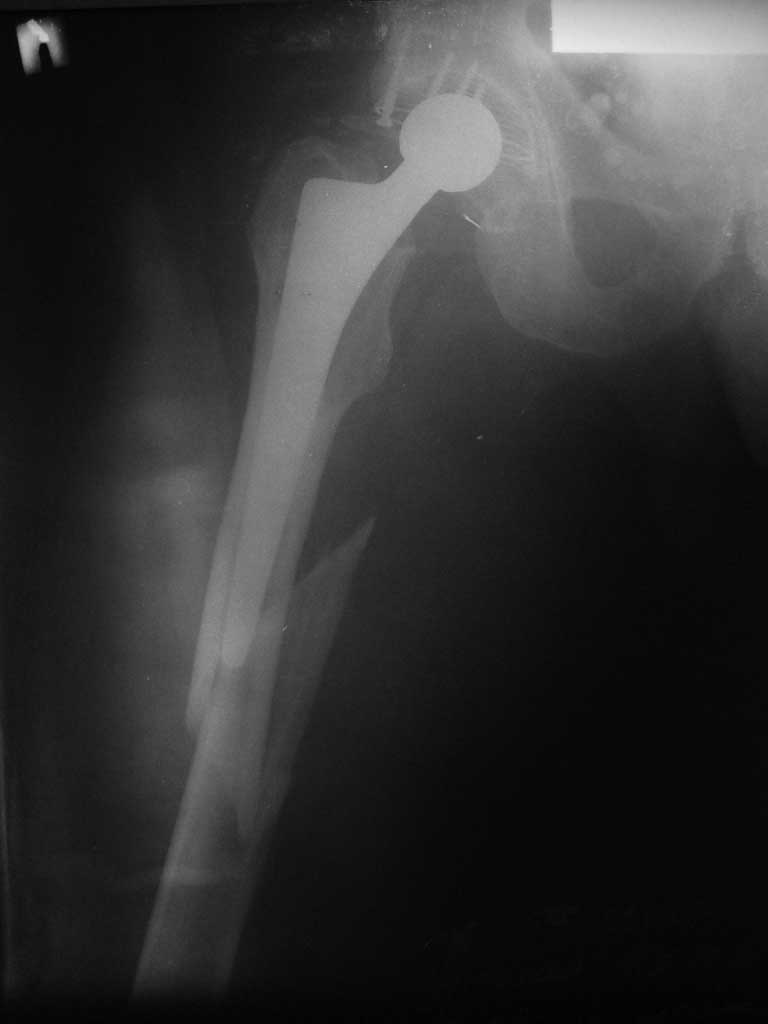

Пациента удалось осмотреть недавно. Достигнутый результат сохраняется. Перелом бедра сросся. Конечность опорная и безболезненная, ходит без трости. Ножка, похоже, реинтегрировалась, как и надеялись. Снимки и фото в приложении. Комментарии приветствуются.

Надо ли что-то делать дальше, как полагаете? Убрать винты? Убрать "удлинитель ножки"? Или оставить все, как есть? Спасибо заранее.

Пациенту 72 года, оперировался 11 лет назад в ГКБ15 Москва. Судя по снимку ножка споторно фирмы матис. Вряд ли сможем найти такую же для примерки.

Дополнительные снимки